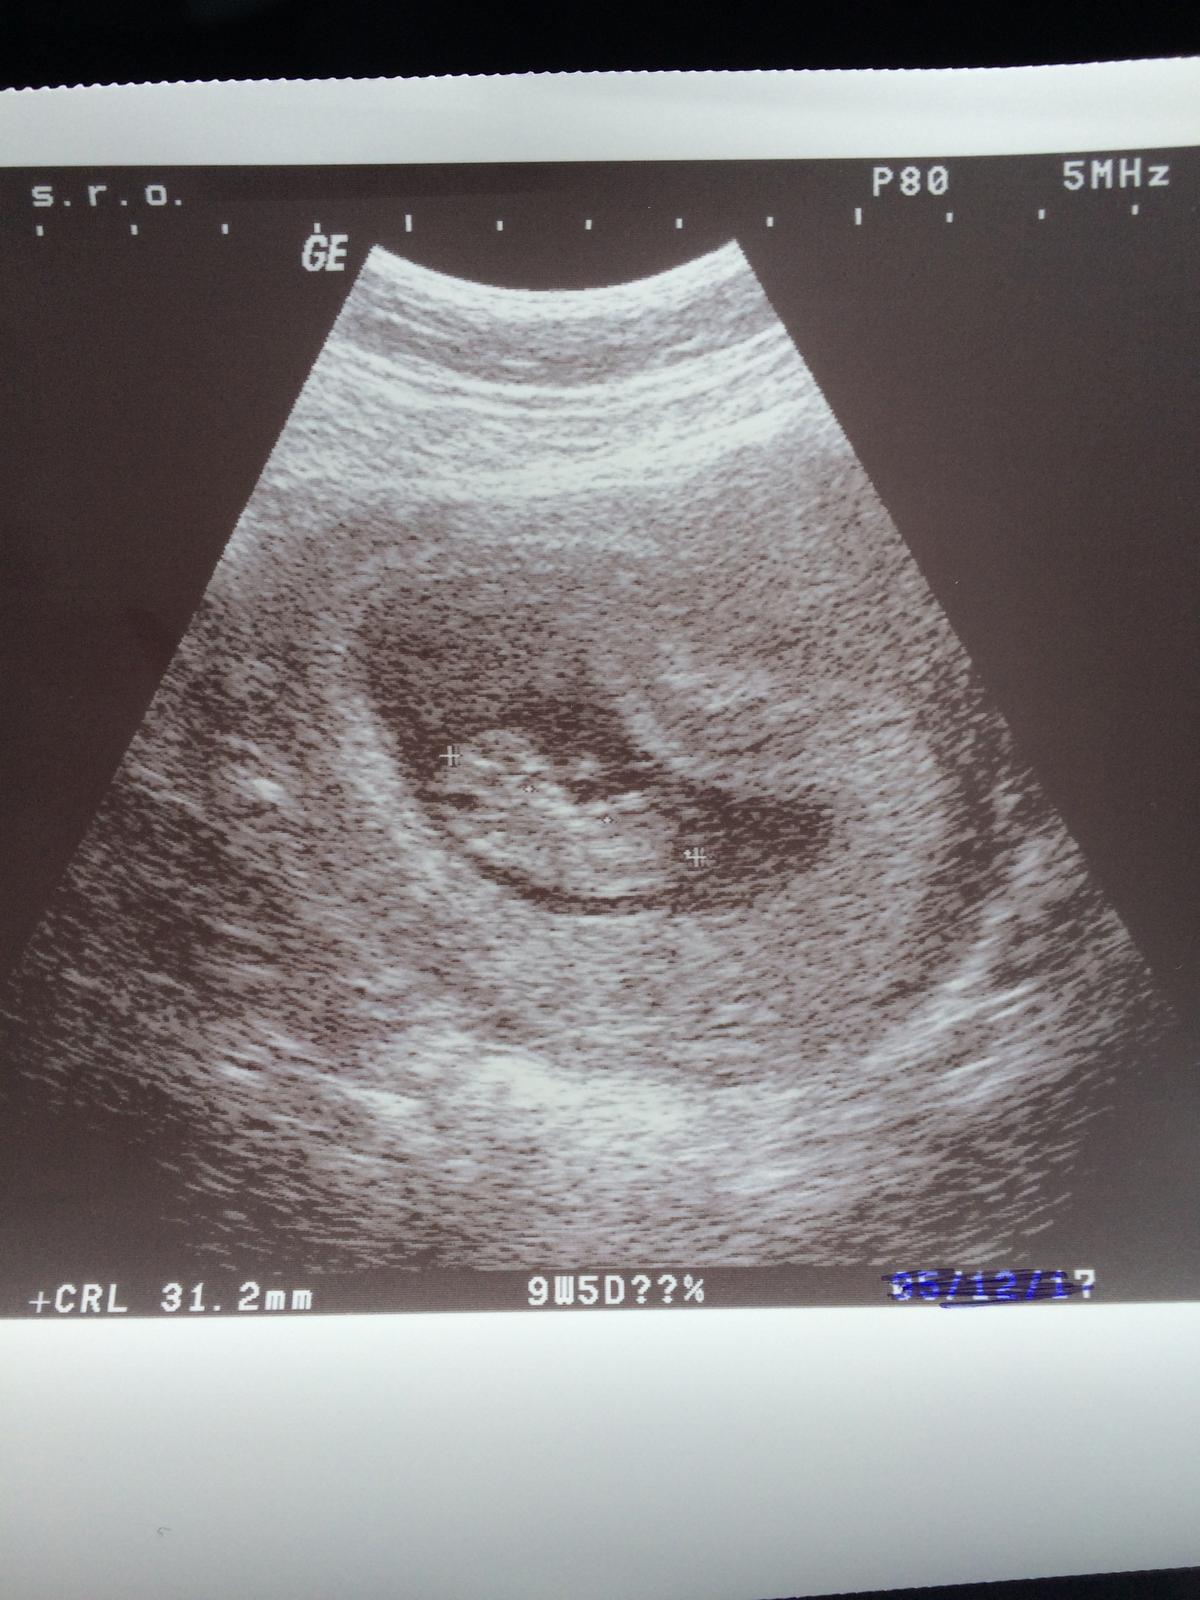

Ahojte babulky, daaavno som tu nebola ale citam vas pravidelne 🙂 dnes som bola na svojej prvej poradni, tak som sa rozhodla, ze sa podelim s vami o fotecku, kedze ste mi pomahali hladat mini dusika na tehu teste 😀 podla sona som 9+5 tt a fazulka ma 31 mm 😍 termin mam posunuty kvoli posunutej ovulke na 1.7.2018 🙂 dievcata, drzim vam vsetkym palce ❤